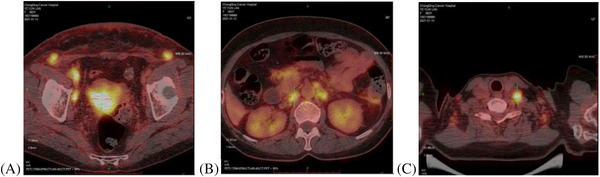

Cervical cancer, the fourth most common cancer among females in the world, ranks the second in China. In advanced disease, metastases may be commonly present in the lungs, bones, liver and lymph nodes or elsewhere, but uncommon to the skin. In this report, a 63-year-old woman was diagnosed as stage IVB cervical squamous cell cancer in January 2021. The patient was scheduled for concurrent chemoradiotherapy; however, a metastatic lesion of skin was proved by biopsy during the process of treatment. She died 1 month after confirmed skin metastases. Cutaneous metastasis of cervical cancer may predict the mix of lymphatic and hematogenous metastasis and the rapid fatal termination.